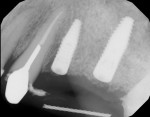

Healing was uneventful. A full 6 months was allowed for hard- and soft-tissue maturation (Figure 10). An implant stability quotient (ISQ) value (Osstell, osstell.com) of 68 for the grafted site was noted at stage II, which is very good for type IV bone (Figure 11). The final restorations were fabricated, consisting of four individual units for teeth Nos. 11 through 14 (Figure 12). The periapical x-ray taken shortly after delivery of the prosthetics depicted osseointegrated implants in position Nos. 12 and 13 (Figure 13). The CBCT revealed that the implant in position No. 13 was well positioned and demonstrated complete regeneration of the buccal plate (Figure 14).